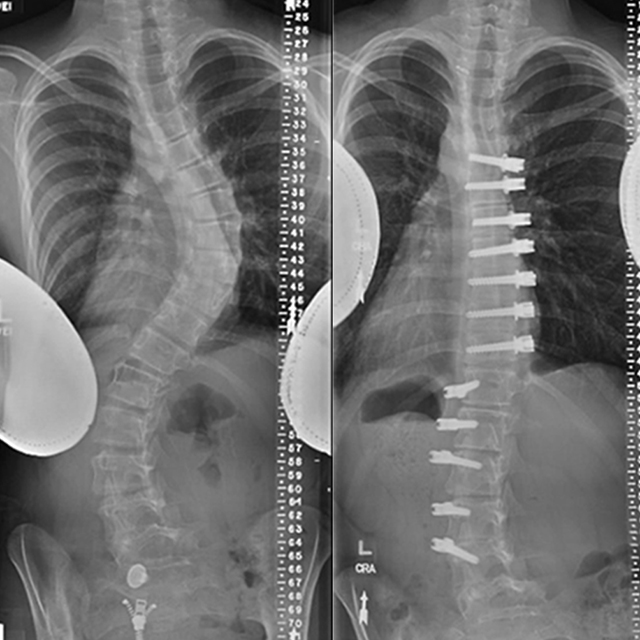

In addition to checking for these differences, the doctor may order X-rays to see the alignment of the vertebrae. These images can be used to determine the degree of spinal curvature and to help monitor its progression over time.

Scoliosis treatment options depend on the degree of curvature of the spine, viewed from the front or back by X-ray. The following are general guidelines for treatment.

Beyond 50 degrees, the spine loses its ability to compensate, and progression becomes inevitable even after physical maturity. The only way to stop progression at this stage is through surgery, either spinal fusion or vertebral body tethering. In spinal fusion surgery, metal implants are used to realign and fuse the vertebrae in a way that corrects the curve.